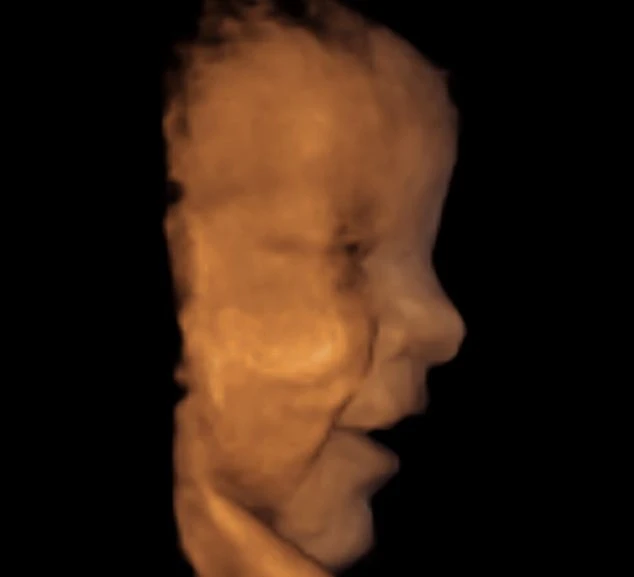

Tấm hình này được chụp lúc bé Alice 26 tuần tuổi, lúc này bàn chân đã hình thành ngón và bé có thể cử động, nghịch ngợm trong bụng mẹ.

Ở thời điểm 26 tuần tuổi, các nét trên khuôn mặt bé đã được hình thành rõ nét, thậm chí bé có thể thể hiện cảm xúc như khóc hay nhíu mày.